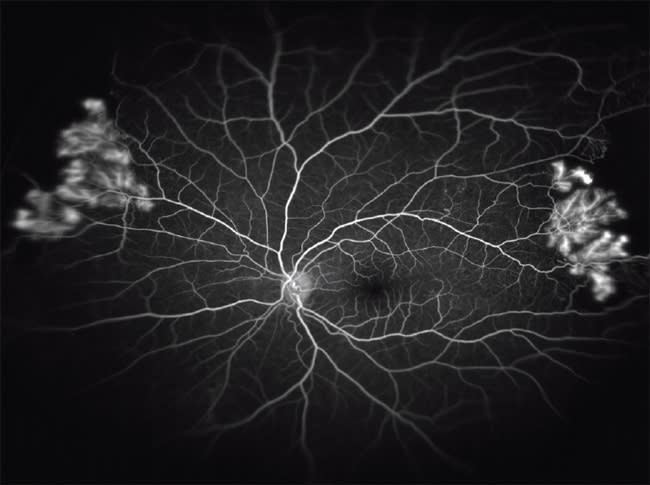

Figure 1. Hydroxychloroquine toxicity with “bull's eye” maculopathy and peripheral pigmentary changes that have never been described before in the literature.